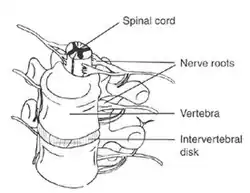

When myelomalacia occurs, the damage done to the spinal cord may range from minimal to extensive. The spinal cord and the brain work together, making them the key components of the central nervous system.[5] Damage to this system affects specific functions of the body, primarily relating to the function of muscles. The areas most commonly injured include the cervical vertebrae (C1-C7), and the lumbar spine (L1-L5).[6]